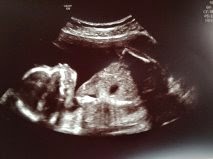

Grattis